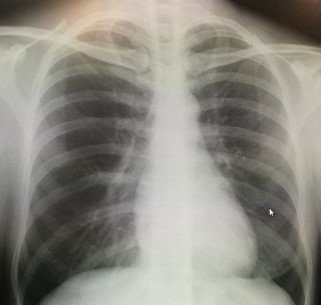

みなさんもよく耳にする呼吸器疾患は「急性肺炎」「誤嚥性肺炎」「慢性閉塞性肺疾患(COPD)」などがあります。国内における死亡原因の上位にある疾患のひとつが「肺炎」。他の病気と合併して発病するのも特徴のひとつです。

腹式呼吸は横隔膜が下がって、2つの肺が均等に膨らむはず。しかし吸った空気の通りが悪くなっている肺の部位があれば厄介です。

例えば気管支の根元で吸気の通りが悪くなっていれば、正常に膨らまない肺の部位が広範囲になってしまう可能性が高まります。どちらか片方の肺が押しつぶされるように歪(いびつ)に膨らむ。効率よく2つの肺で均等にガス交換ができません。